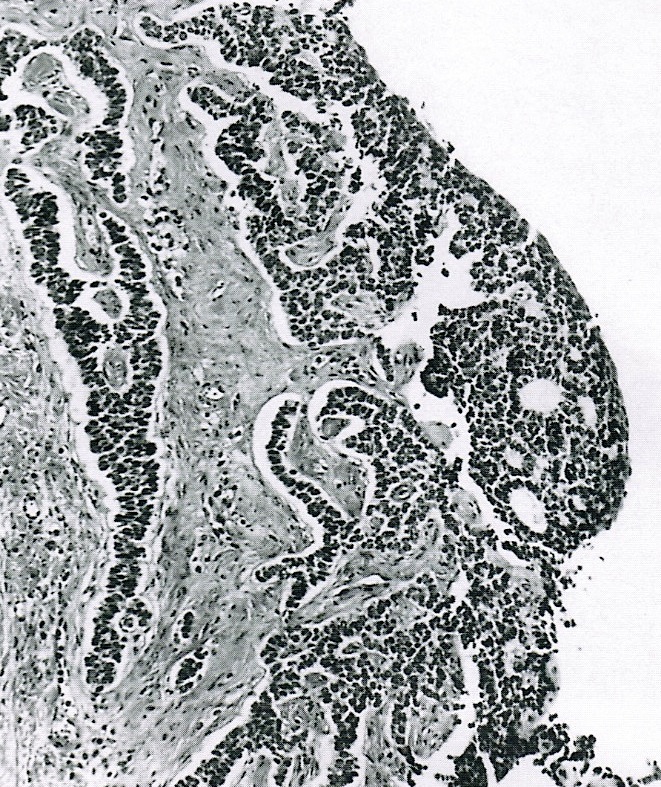

- Small, bland, cuboidal to polygonal cells with scant cytoplasm and pale, uniform angulated and usually grooved nuclei (coffee bean)

- Various patterns, including diffuse (the most common), trabecular and corded, insular, microfollicular (resembling Call-Exner bodies of the Graafian follicles: small follicle-like structures filled with eosinophilic material) and macrofollicular (the least common)

- Usually a mixed growth pattern is seen

- Predominantly cystic granulosa cell tumor or macrofollicular pattern may mimic ovarian follicle

Microscopic (histologic) images

Contributed by Shabnam Zarei, M.D. and Sharon Bihlmeyer, M.D.

AFIP images